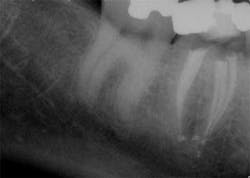

The success of endodontic treatment is directly related to the clinician’s ability to remove maximum numbers of bacteria from the root canal system. (1,2) If we can agree that all root canal treatment is associated with a certain degree of skill and precision in spite of perceived ease of treatment, I think it is fair to say there are no easy root canals. Some teeth are more difficult than others due to access limitations or anatomy, but the problem that faces all of us, in every tooth, is our inability to measure the absence of bacteria within the root canal and the potential for microanatomy to exist at any level of the root—whether it is a five-canal molar or a single-rooted anterior. It is impossible to determine the exact terminus of the root canal system, and there is no uniform agreement about where the root canal system ends. (3,4) The use of an apex locator can aid in this determination, but there is often disagreement between radiographic information and an apex locator, even in single-rooted anterior teeth, because the canal terminus can be at the radiographic apex or as much as 3 mm from it. (5) All instrumentation techniques leave a certain amount of the canal wall untouched, and we are not able to sterilize the root canal system. (6,7) The apical portion of any tooth may have dentinal tubules that can harbor bacteria, and the concept of a single uniform canal opening at the apex is anything but accurate. (8,9) Many teeth will have multiple portals of exit that may or may not be present in the apical third of the root. (Figure 1) As a result, the clinician must assume the apical canal anatomy in every tooth is highly variable in size, shape, and number (10,11,12) and there are no “easy ones.”

maxillary central incisor with a necrotic pulp. A prominent lateral canal can be seen,

but there is no way to know if multiple microscopic branches are present at any level

of the root canal system.